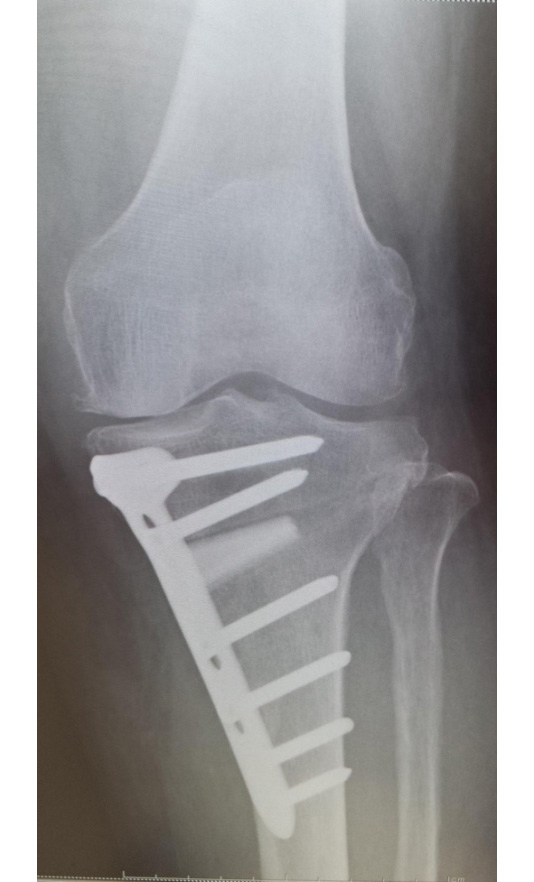

当院でおこなった高位脛骨骨切り術

手術直後